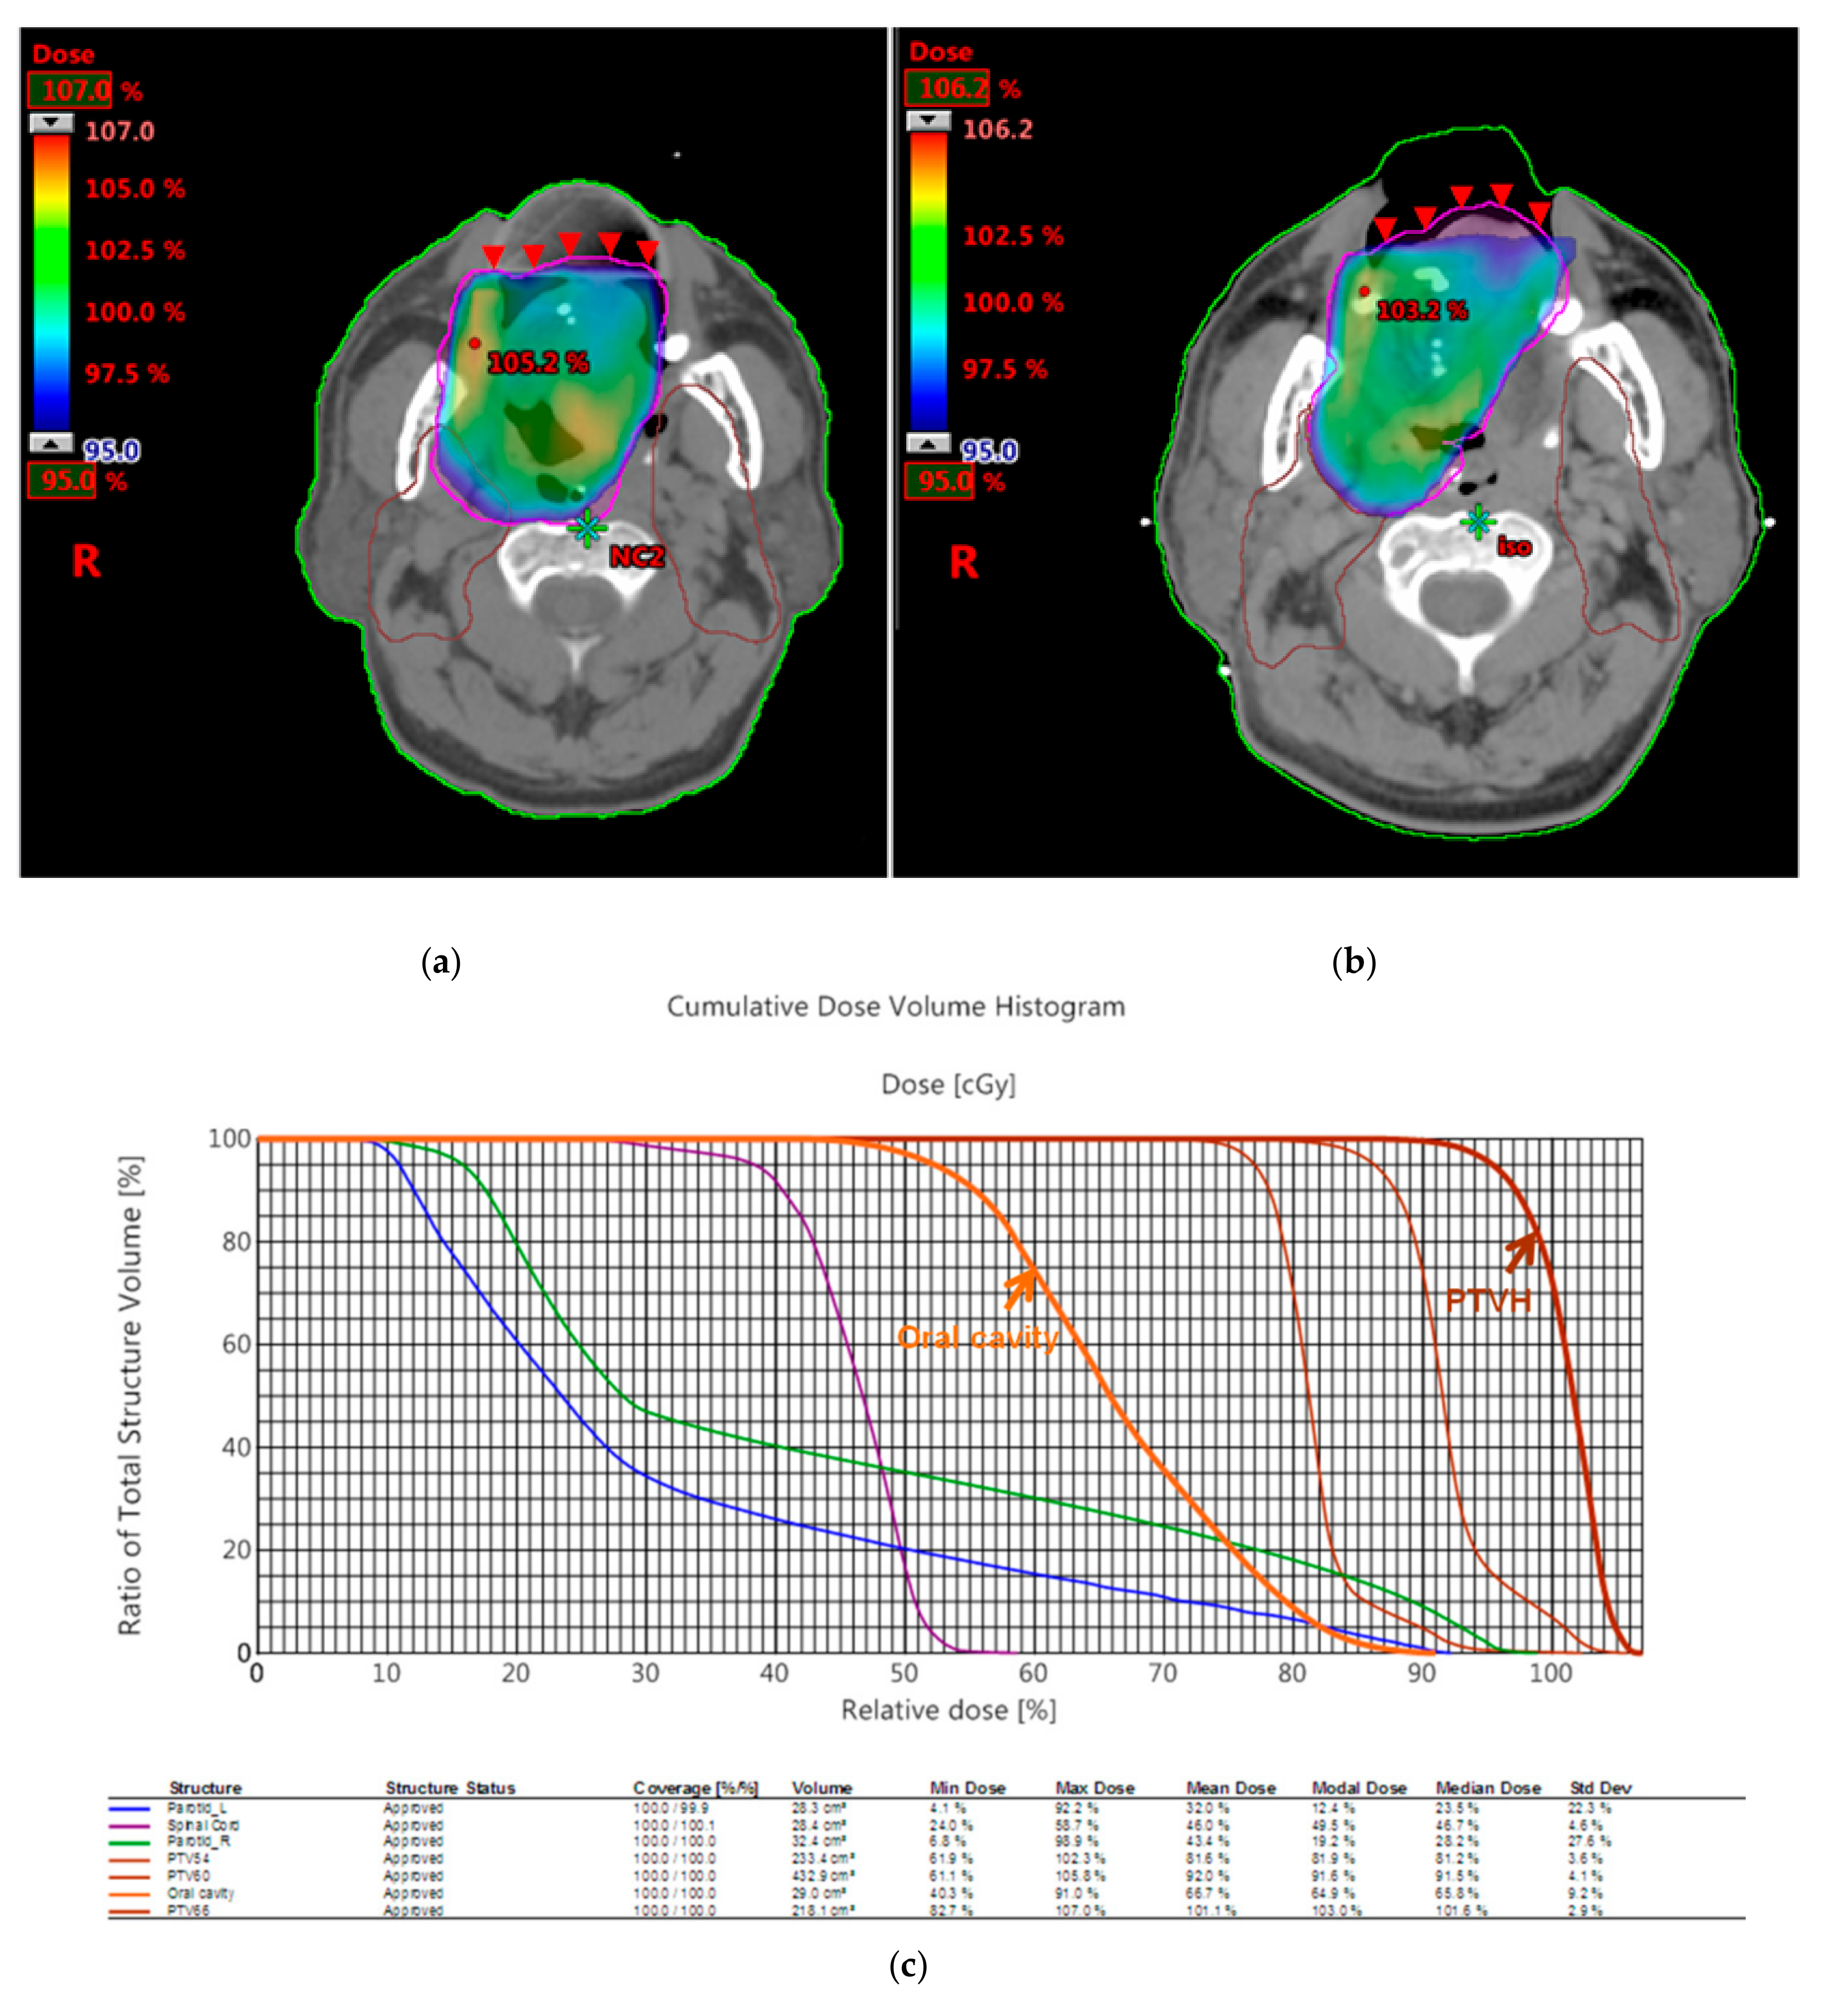

3.2. Dosimetric Comparison

| Patient 1 | 3D Printed Bite Blocks | Conventional Oral Corks |

|---|---|---|

| PTV D100% | 95% | 95% |

| PTVmax | 107% | 106.2% |

| PTVmin | 82.7% | 76.8% |

| CI | 0.96 | 0.94 |

| HI | 1.13 | 1.12 |

| Median dose of oral cavity | 45.7 Gy | 48.6 Gy |